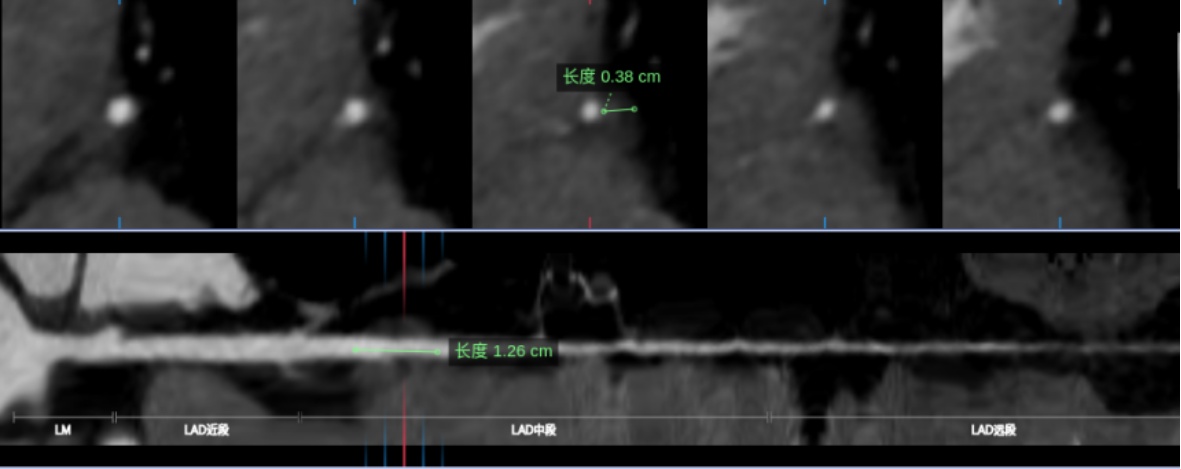

在本研究中,MB-MCA的长度与厚度测量均基于CCTA的收缩期图像进行,以准确反映心肌收缩时对血管的压迫特征。将所有冠状动脉图像数据导入后处理工作站,运用多平面重建(MPR)和曲面重建(CPR)等技术进行形态学参数提取。MB厚度的测量在垂直于MCA走行的MPR图像上进行,于收缩期选取心肌桥压迫最深的位置,测量从心肌外膜至动脉血管外侧壁的最大垂直距离,作为MB厚度[7]。MB-MCA长度的测量则在CPR图像上完成,于收缩期确定其入口(即开始被心肌覆盖的位置)与出口(心肌覆盖结束的位置),测量该段血管的长度即为MB-MCA长度(图2) [8]。为减少心肌桥导致的血管位移伪影对测量准确性的影响,本研究采用以下质量控制措施:① 所有图像均在收缩期重建,以最大程度减少运动伪影;② 对于图像中存在明显阶梯状伪影或血管边缘模糊者,予以排除;③ 所有测量均在MPR与CPR图像上反复确认,确保测量平面垂直于血管走行。所有测量工作由一名具有5年及一名具有8年CCTA诊断经验的心胸影像诊断医师独立完成。采用组内相关系数(ICC)进行观察者间一致性检验,结果显示两位观察者的测量结果一致性极佳(ICC > 0.90)。对于极少数存在分歧的测量结果,经协商后取得共识,并取其平均值作为最终结果,确保数据的客观性与准确性。此外,为确保两家医院数据的一致性,所有图像均由同一组专家采用统一的标准化流程进行后处理与测量,并进行了观察者间和观察者内的一致性检验(ICC > 0.90)。

Figure 2. Measurement methods of MB-MCA length and MB thickness

2. MB-MCA长度与MB厚度的测量方法

3.4. FAI测量

将患者收缩期原始图像上传至数坤网络科技人工智能平台进行分析,测量FAI值。FAI值以MCA-MB入口近端2 cm为纵向距离,以血管外壁直径为径向距离,测量范围为血管外壁到外圈周围组织。调整纳入计算的组织密度范围为−190~−30 HU,随后软件自动计算出斑块血管周围脂肪密度的平均值作为FAI (图3)。

Figure 3. Measurement method of FAI

3. FAI的测量方法